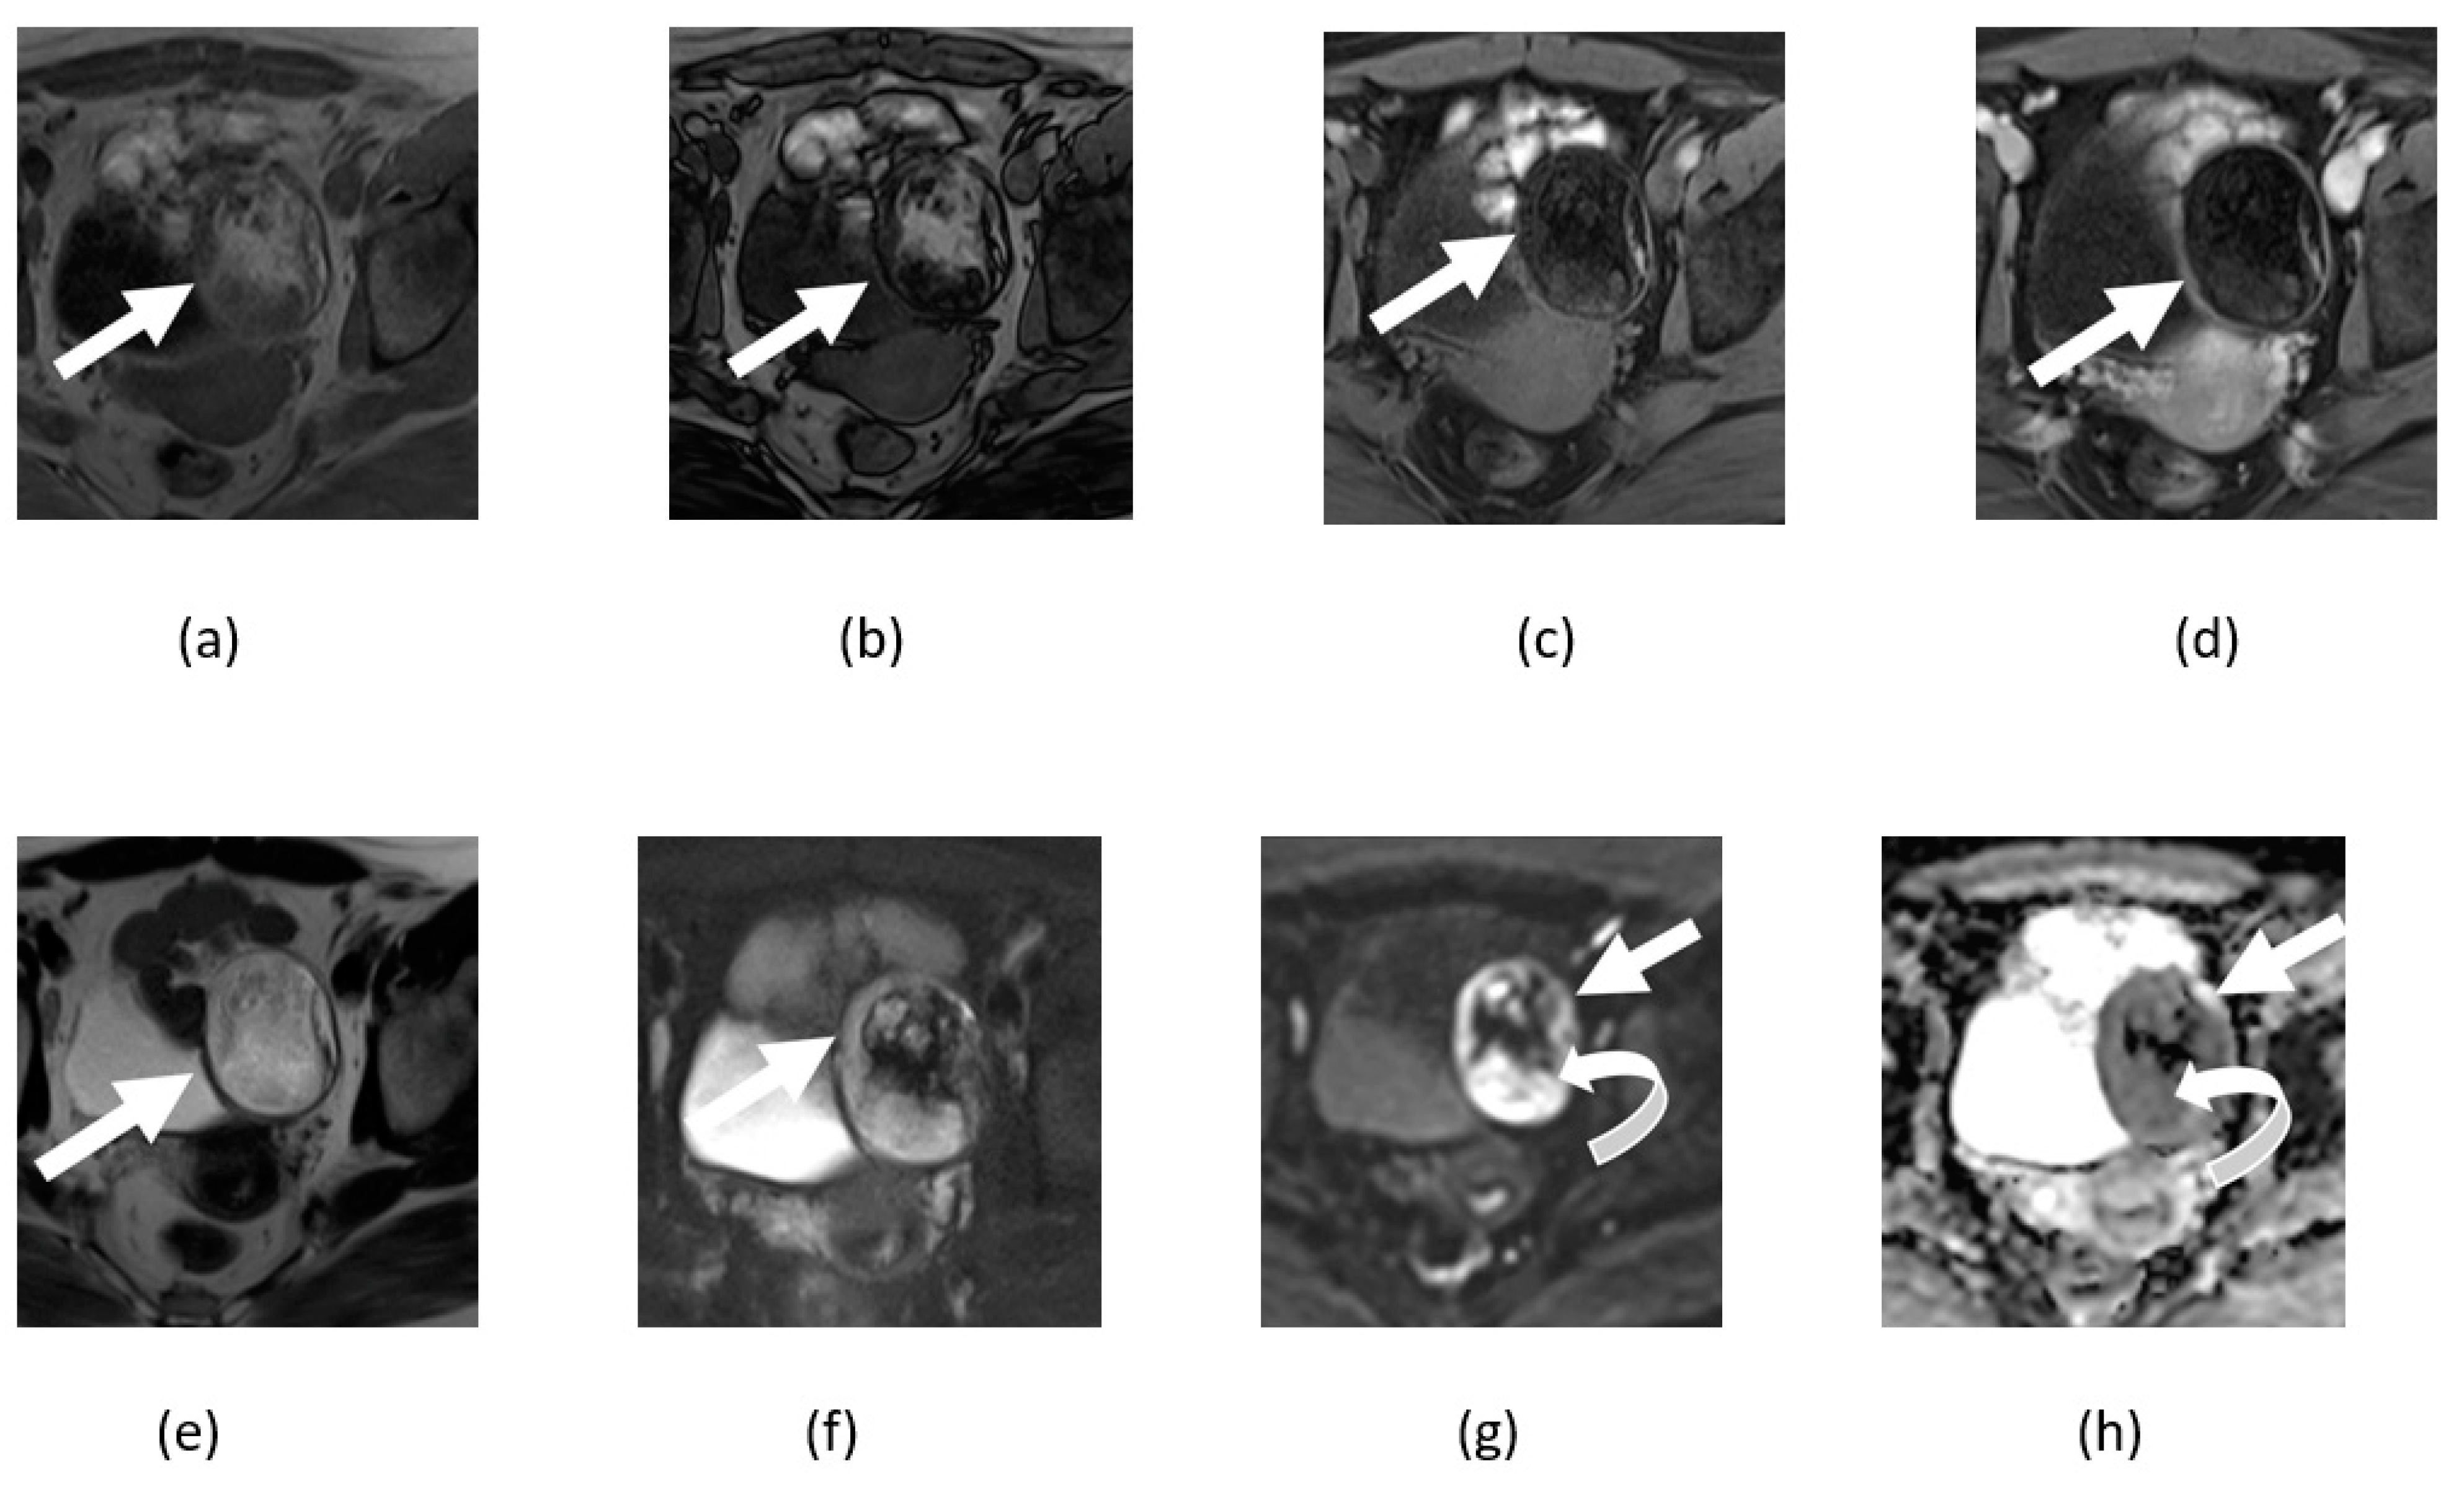

4.3. Ovarian Cancer

5. Pitfalls of DWI